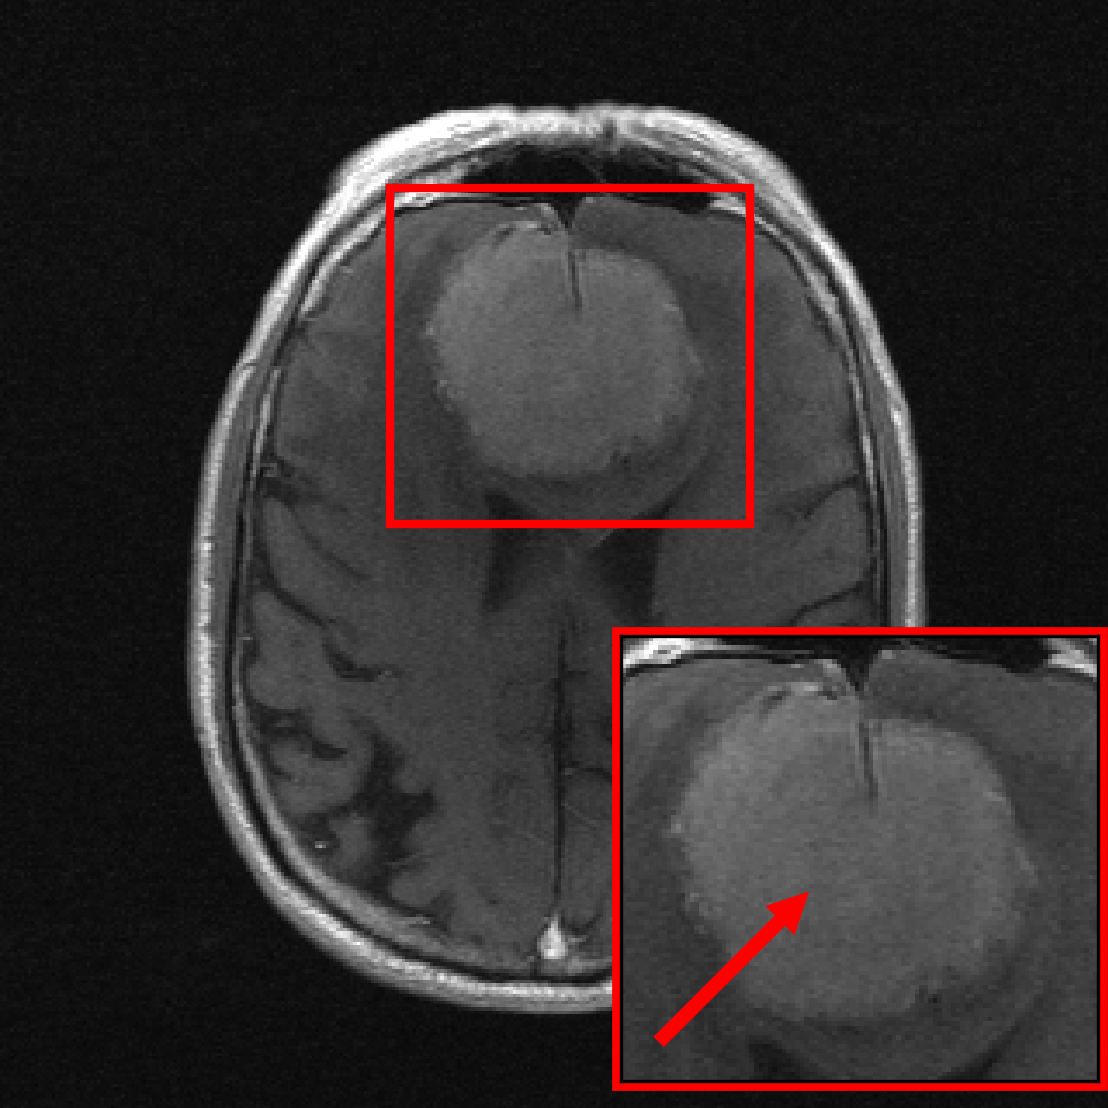

Taken together, those four findings suggest that training a single model on a diverse set of data distributions and incorporating early stopping yields a robust model. We test this hypothesis by training a model on a large and diverse pool of data significantly larger than the fastMRI dataset \citepzbontarFastMRIOpenDataset2019a. The resulting model, as shown in Figure 1, is significantly more robust than a model trained on the fastMRI dataset, the single largest dataset for accelerated MRI, without compromising performance on fastMRI data.

7 Robust Models for Accelerated MRI

The results from the previous sections based on the fastMRI dataset suggest that training a single model on a diverse dataset consisting of several data distributions is beneficial to out-of-distribution performance without sacrificing in-distribution performance on individual distributions.

We now move beyond the fastMRI dataset and demonstrate that this finding continues to hold on a large collection of datasets, enabling significant out-of-distribution performance improvements. We train a single large model for 4-fold accelerated 2D MRI on a diverse collection of 13 datasets including the fastMRI brain and knee datasets, and evaluate on 4 out-of-distribution datasets (the descriptions of the sets are in Table 1). The resulting model, when compared to models trained only on the fastMRI dataset, shows significant robustness improvements while maintaining its performance on the fastMRI dataset.

Figure 10 shows for all architectures considered, the model trained on the collection of datasets significantly outperforms the models trained on fastMRI data when evaluated on out-of-distribution data, without compromising performance on fastMRI data. For example, on the CC-359 sagittal view dataset, the VarNet trained on almost closes the distribution-shift performance gap (i.e., the gap to the model trained on the out-of-distribution data). We refer to Figure 1 and Figure 21 (in the Appendix) for reconstruction examples.